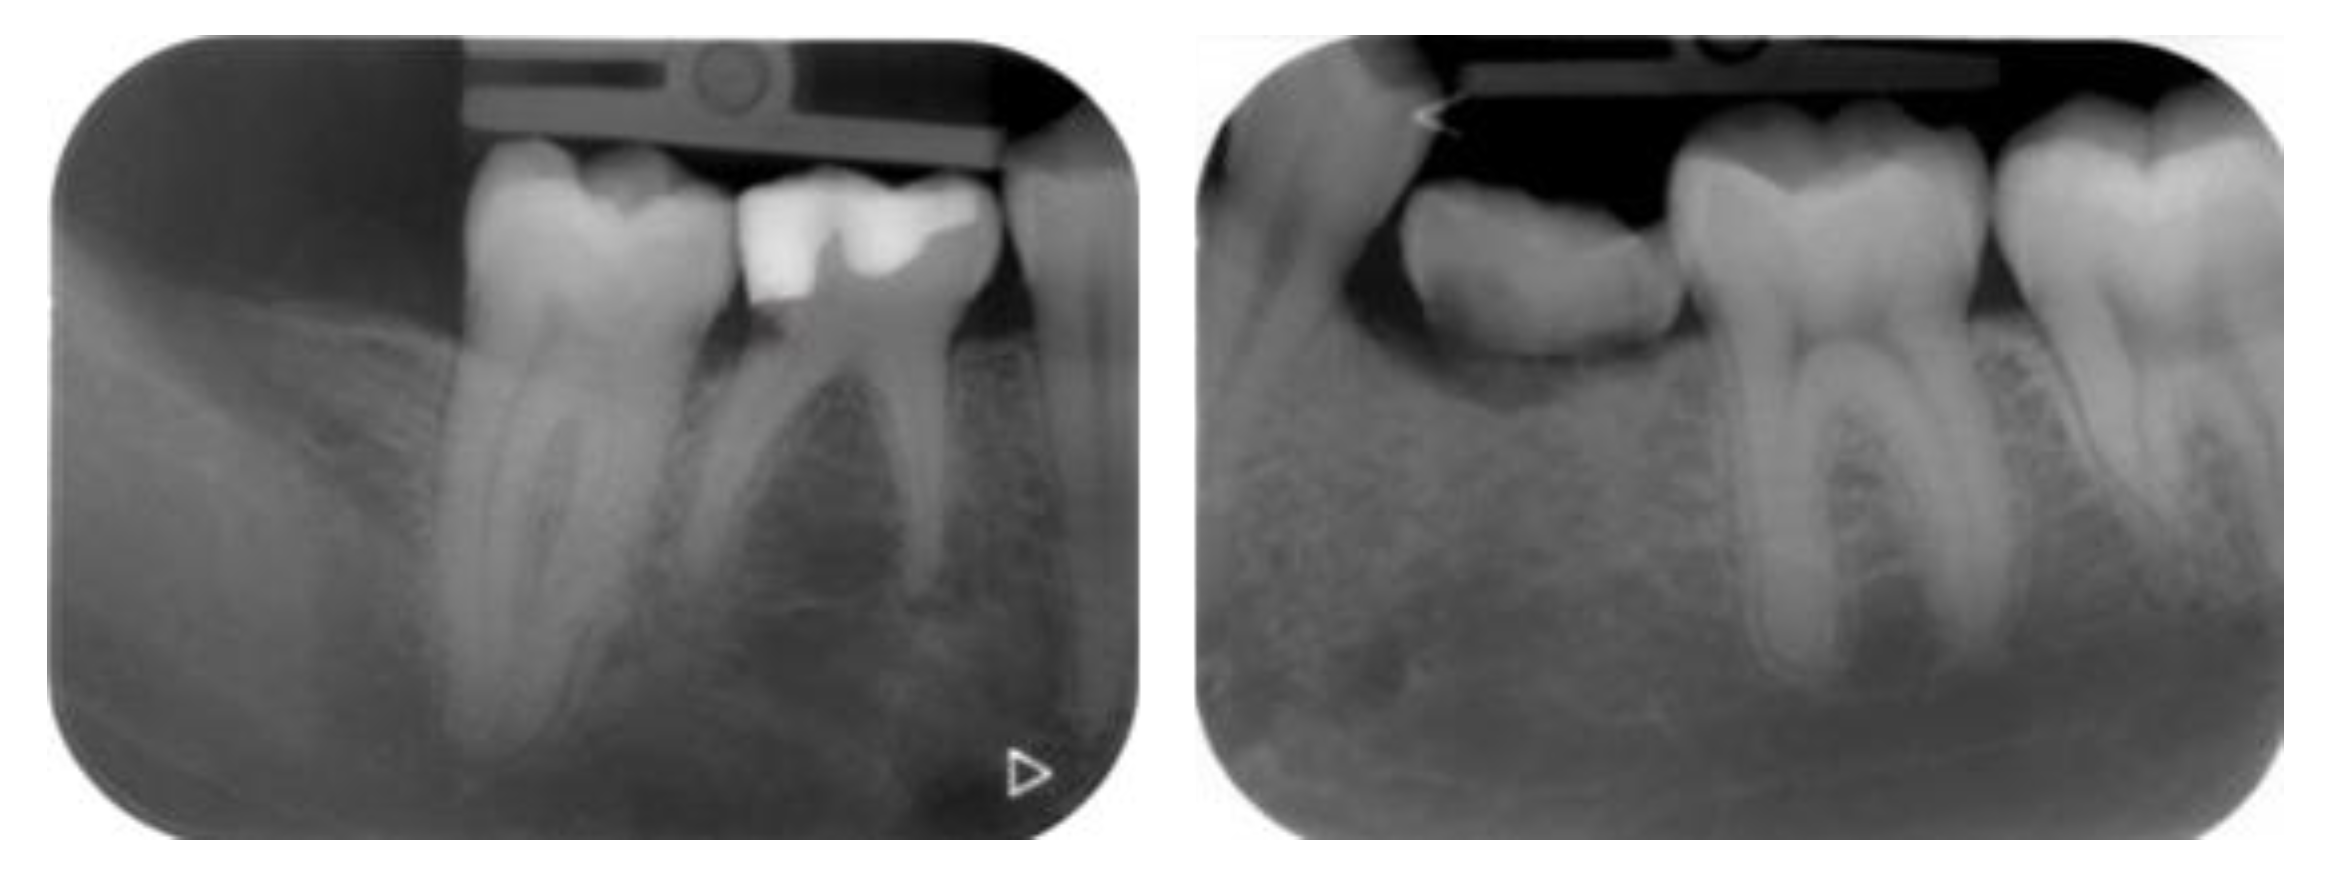

2.4.1. Radiographic Measurements

- Case 1:

- Case 2:

- Case 3:

- Case 4:

- Case 5: